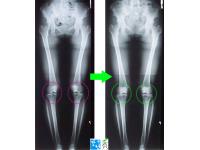

• 교정전후사진